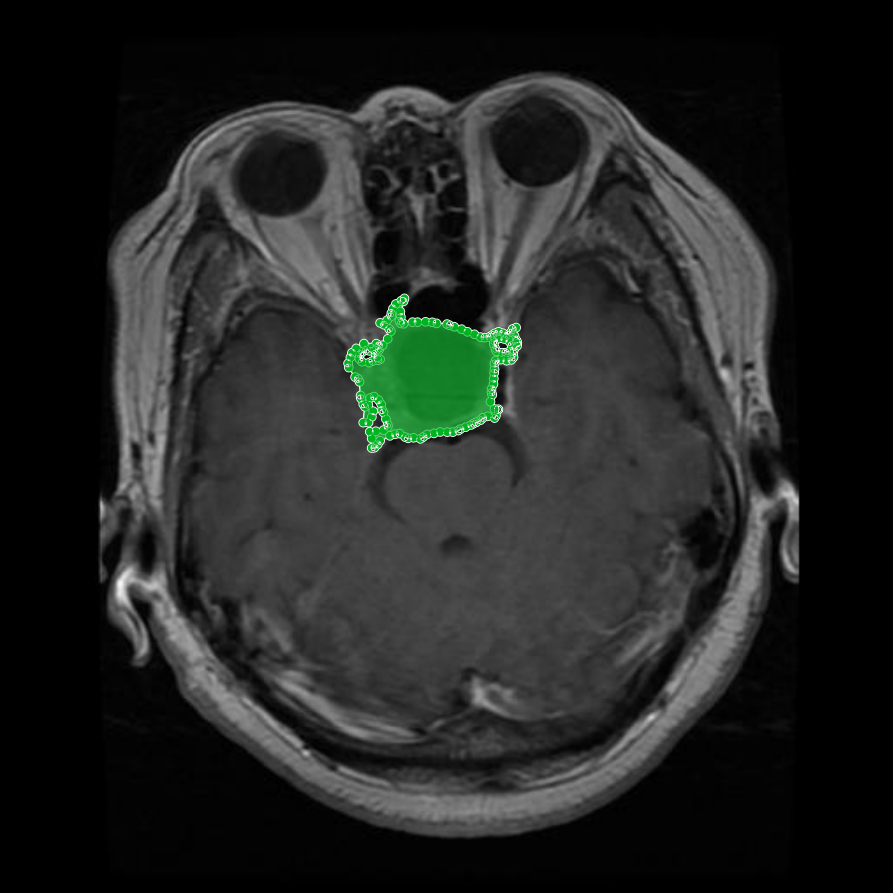

Figure 1: Samples of Glioma segmentation across different imaging planes

Glioma: Gliomas are irregularly shaped and often infiltrate surrounding tissues, presenting significant challenges for precise boundary definition. These complexities require robust segmentation techniques to capture their variable morphology. As shown in Figure 1, gliomas exhibit irregular and diffuse growth patterns, which are highlighted through annotated tumor masks.

Meningioma: Meningiomas arise from the meninges and are generally well‑circumscribed and homogeneous, making them easier to segment. However, their location adjacent to critical structures such as dural sinuses and cranial nerves can complicate diagnostic tasks. An example of a meningioma and its segmentation mask is presented in Figure 2, illustrating the clarity of its boundaries.